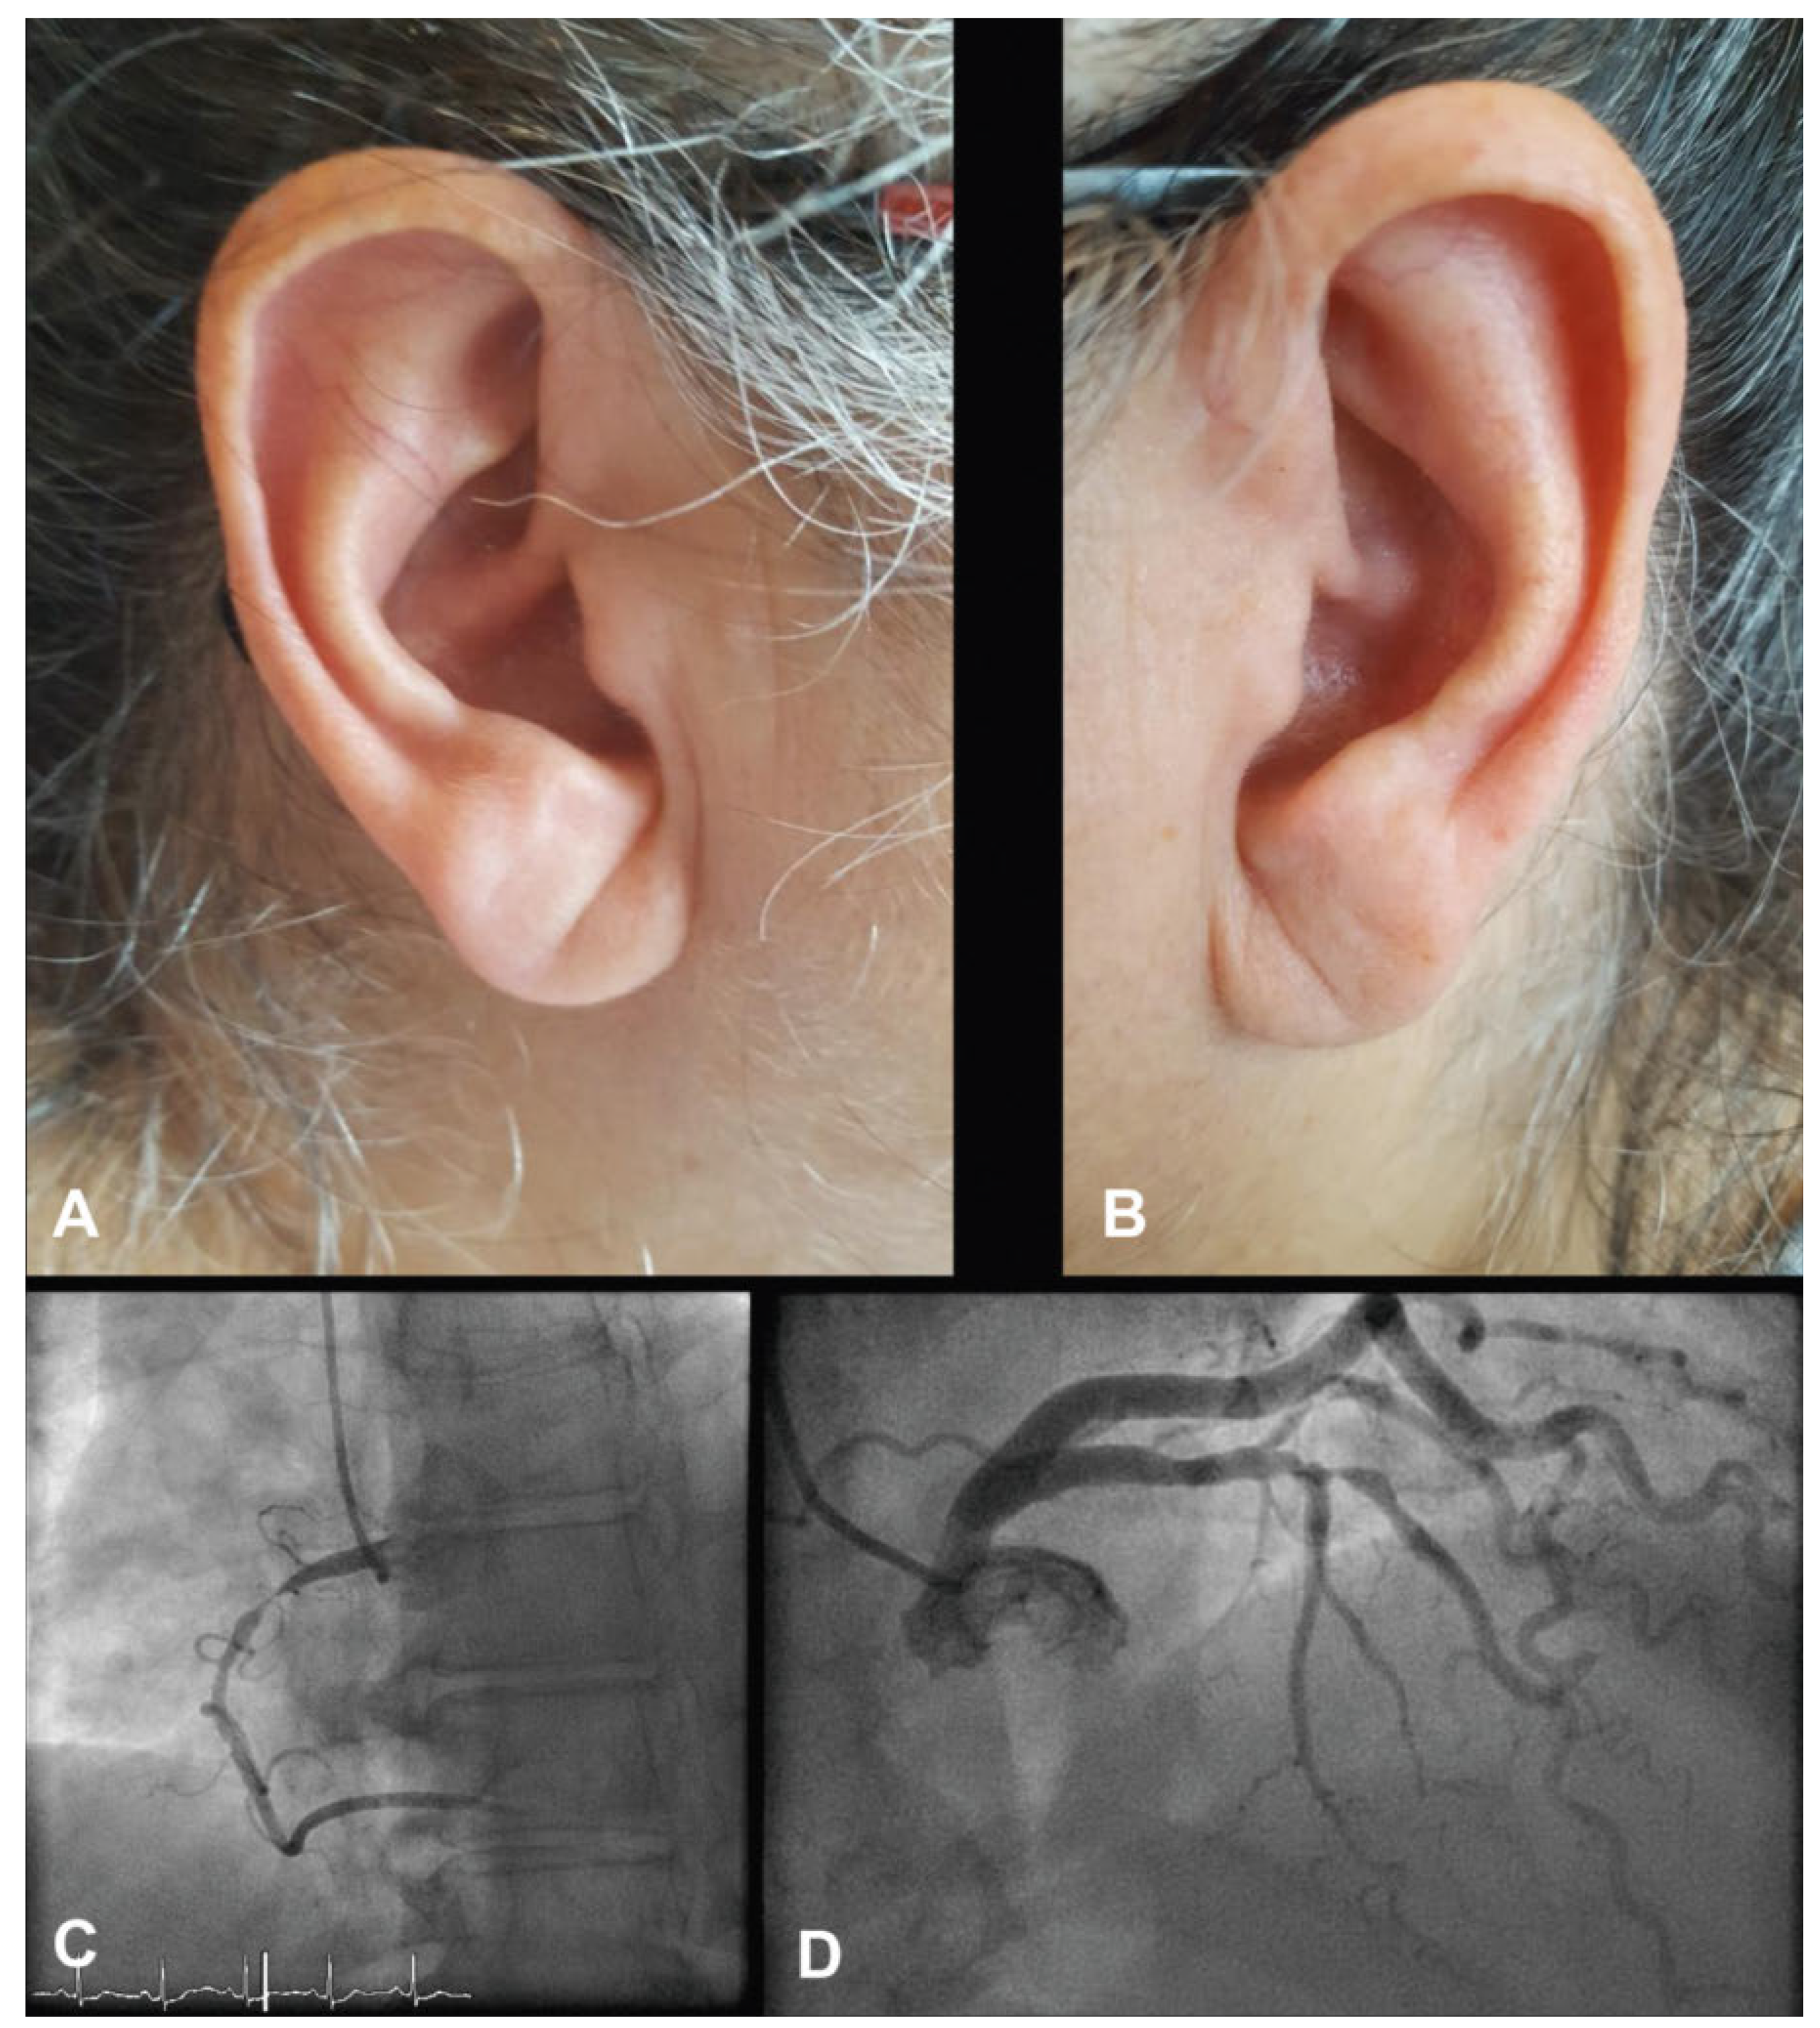

Franck’s Sign

Case Description